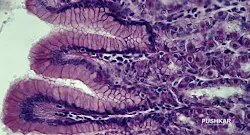

ГИПОХЛОРГИДРИЯ – НИЗКИЙ УРОВЕНЬ ЖЕЛУДОЧНОЙ КИСЛОТЫ ИЛИ ПОНИЖЕННАЯ КИСЛОТНОСТЬ ЖЕЛУДКА.

Потребность человека в витаминах, минералах и других питательных веществах остается относительно постоянной на протяжении всей жизни. К сожалению, наша способность правильно переваривать пищу и поглощать жизненно важные питательные вещества снижается с возрастом. Одной из наиболее распространенных возрастных причин нарушения пищеварительной функции является уменьшение соляной кислоты, вырабатываемой желудком.

Из этого протокола вы узнаете не только о причинах низкой кислотности желудка, но также о том, как диета и образ жизни могут помочь избежать и вылечить состояние. Будут обсуждаться традиционное лечение, а также рекомендации по питанию.